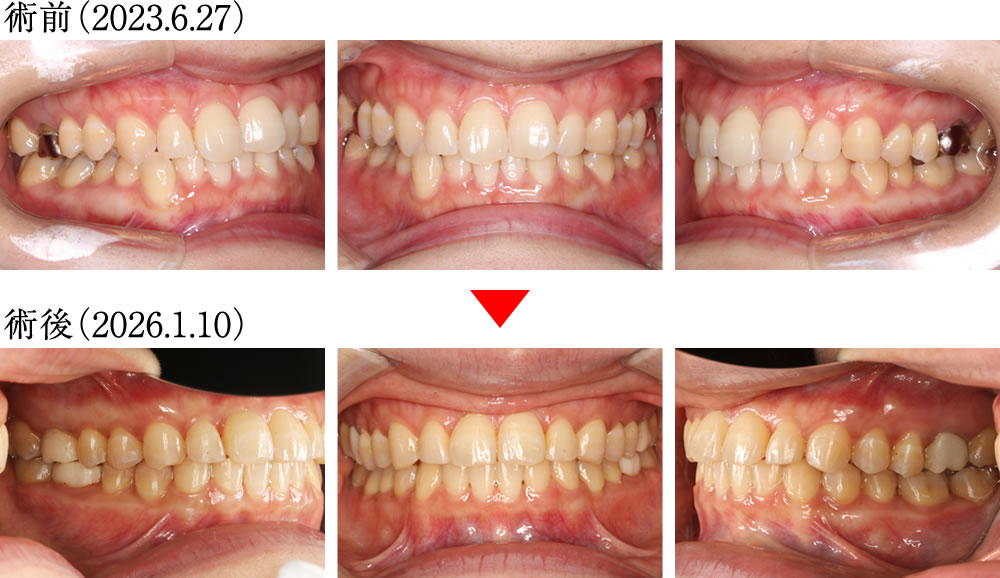

矯正治療終了

術前は上下顎の正中がずれており、右下の犬歯が飛び出している歯並びでした。術後は上下の正中が揃い、理想的な被蓋関係で咬み合う、きれいな歯並びになりました。

術前は歯が重なり合うように乱れた狭い歯並びでしたが、術後は歯が理想的に並び、きれいでバランスの良い大きなアーチの歯並びへと改善しました。